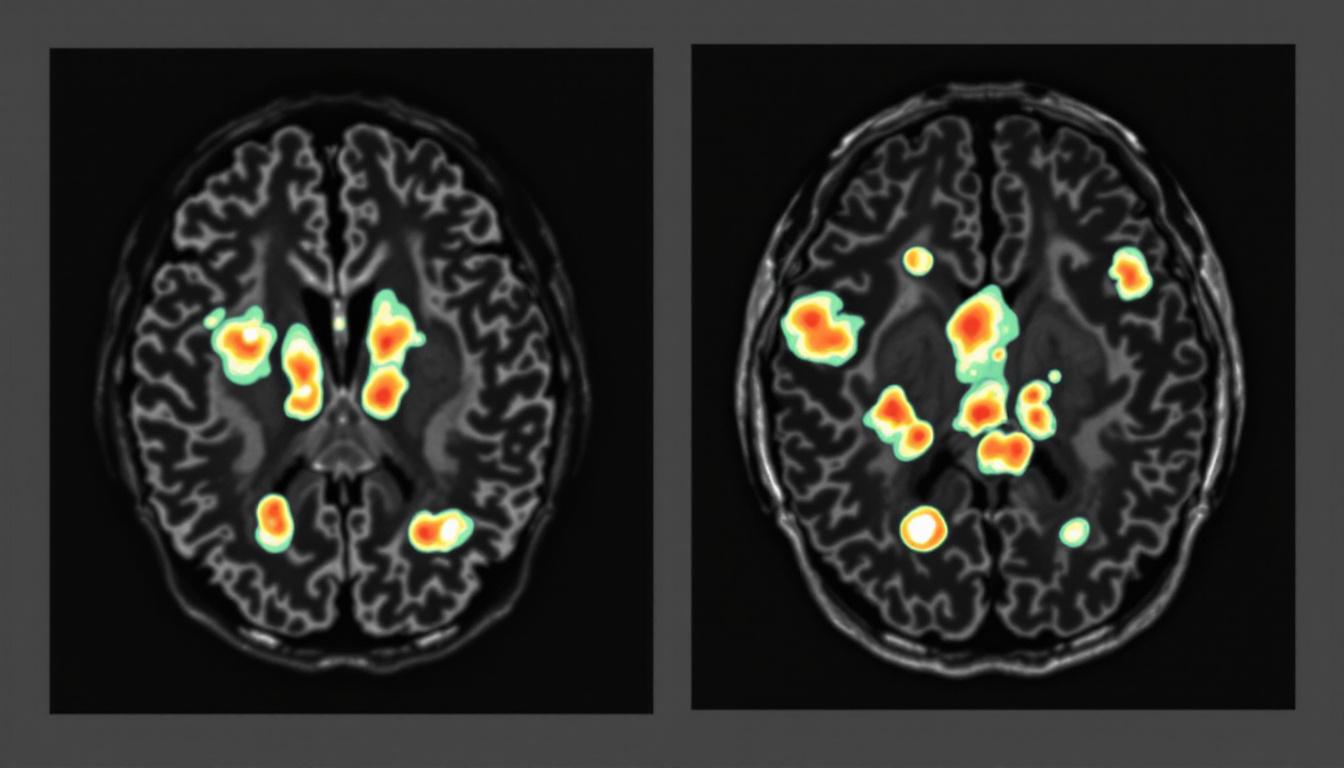

L’échelle de Fazekas est un outil diagnostique crucial pour évaluer les lésions de la substance blanche via IRM, divisées en trois grades, Fazekas 2 se situant au milieu. Ce stade, qui indique des lésions modérées, touche des zones cérébrales étendues, notamment les régions frontales et pariétales, et se manifeste souvent par des signaux hyperintenses sur les séquences T2 et FLAIR. En pratique, ces manifestations peuvent se traduire par des troubles cognitifs légers, des modifications motrices et des altérations de la marche. Les symptômes demeurent une source d’inquiétude car ils signalent une perturbation des circuits neuronaux, avec un risque accru de déclenchement de phénomènes plus graves tels que la dépression ou des troubles neuropsychiatriques.